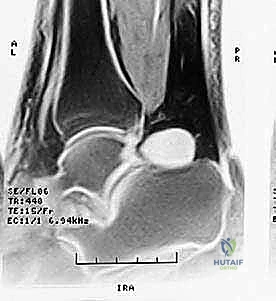

شكل 3: صورة رنين مغناطيسي (MRI) تظهر بوضوح التورم والالتهاب (اللون الأبيض الساطع) في الأنسجة الرخوة والعظم المثلثي في الجزء الخلفي من الكاحل.